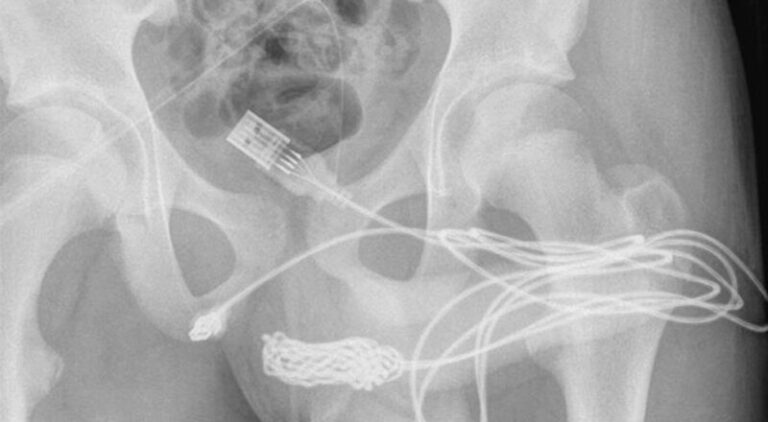

Dječak iz Velike Britanije pokušavao je da izmjeri unutrašnjost svog polnog organa kablom kao oblik “seksualnog eksperimentiranja” kada se začepio i nije mogao da ga izvadi.

Sa čvorovima i zapetljanjima u kablu, dječaku je mokraća bila krvava, a majka ga je odvezla u bolnicu.

“Otkriveno je da dva distalna porta USB žice vire iz vanjskog uretralnog kanala, dok je srednji dio čvoraste žice ostao unutar uretre. Pacijent je inače bio sposoban i zdrav adolescent bez istorije poremećaja mentalnog zdravlja”.

“Urađen je uzdužni peno-skrotalni rez preko palpabilnog stranog tijela i obavljena je pažljiva disekcija kroz dublja tkiva, cijepajući bulbospongiozni mišić. Oba kraja žice su uspješno izvučena kroz vanjski uretralni kanal”.

Međutim, dječak će morati biti pod nadzorom zbog dugotrajnih oštećenja, a u izvještaju se upozorava da ubacivanje stranih predmeta u mokraćnu cijev može uzrokovati bol prilikom mokrenja, pojavu krvi u mokraći, bolne erekcije i zadržavanje mokraće.